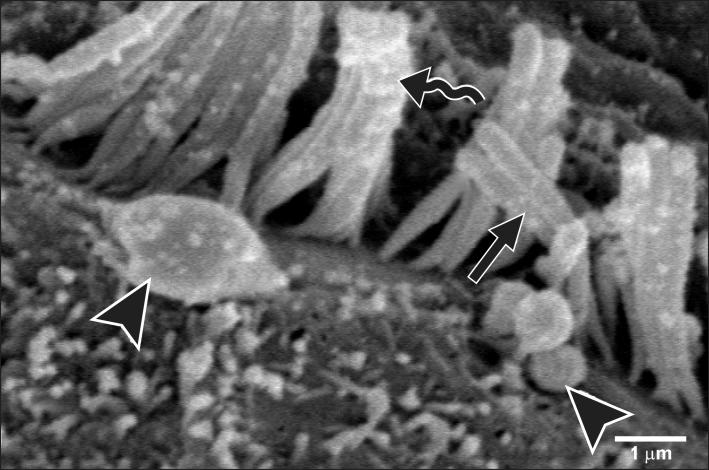

Smoking has been positively associated with hearing loss in human. However, its effect on the cochlea has not been previously evaluated. Aim of work is to investigate the effect of nicotine, which is the primary pharmacological component of tobacco, on the structure of the cochlea of adult male guinea pigs. Fifteen male guinea pigs were classified into two groups: group I (control) and group II (nicotine treated group). Group II was further subdivided into two subgroups; IIA and IIB according to the dose of nicotine (3 mg/kg and 6 mg/kg, respectively). The cochlea was harvested and processed for light microscopy, transmission electron microscopy and scanning electron microscopy. Nicotine administration induced damage of outer hair cells which were distorted in shape with vacuolated cytoplasm and heterochromatic nuclei. Topography revealed damage of the stereocilia which included disorganization, bent and limp or complete loss and expansion of the surrounding supporting cells. These changes were more pronounced in the basal turn of the cochlea and mainly involved the outer hair cells. High dose induced more damage and resulted in protrusion of the apical poles of hair cells (blebing), particularly the outer two rows. Nicotine is proved to be harmful to the cells of the cochlea, particularly the outer hair cells of the basal turn. High doses induce blebing of hair cells.